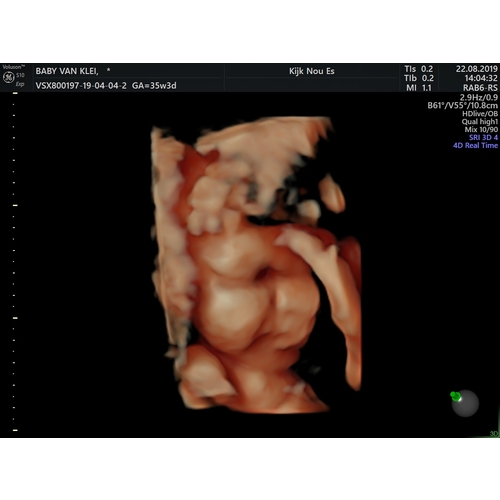

Als je op de Facebook pagina van Kijk Nou Es gaat kijken dan zie je met hoeveel weken hun een 3D echo hebben gedaan. Sommige zijn ook met de 38 weken en die waren echt mooi. Het ligt natuurlijk aan hoe je baby ligt en of die mee wilt werken 😅

Ik heb het gedaan met 32 weken en bij de vk met 36.0.. prachtig beeld, kon hem zo goed zien!